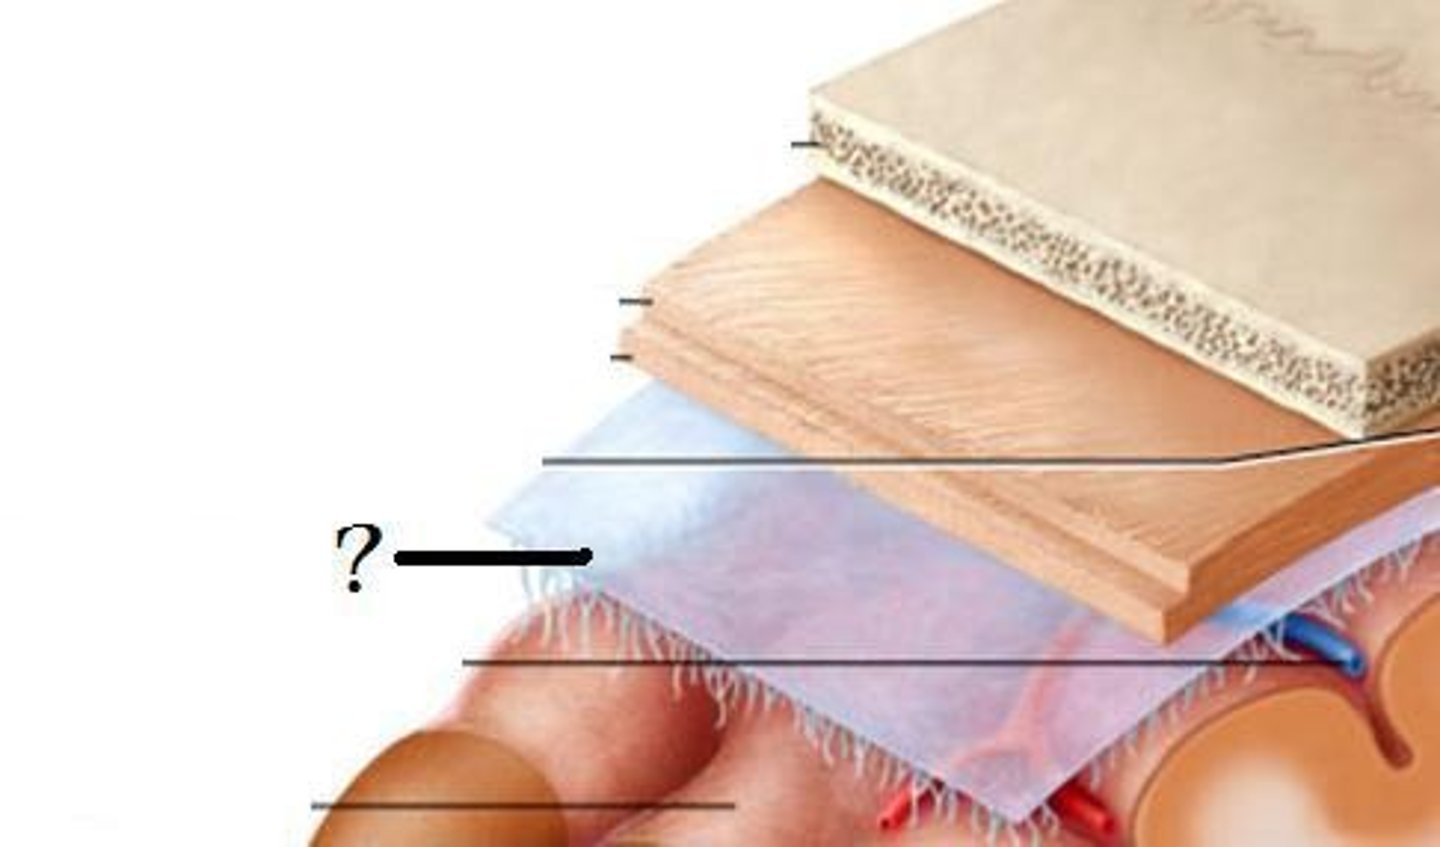

Dura mater

What is this?

Arachnoid mater

What is this?

pia mater

What is this?